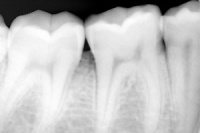

牙齿的X线片简称为“牙片”,也称口内标准片。其面积为3×4平方厘米。一张牙片可以显示3-4个牙齿。牙齿在牙片上显示出白色阻射影像。其中牙釉质阻射最强,牙本质牙骨质阻射低于牙釉质。牙髓腔呈黑色透明影像,根管口根尖孔呈逐渐变细的影像。

牙片是口腔科应用最广的检查手段,也是最常用的,因为它在牙的治疗前、治疗中和治疗后都有助于诊断和治疗。治疗前有助于发现病变;治疗中可用插针照相方法了解扩根情况等;治疗后观察疗效等。

临床上,利用牙片对牙齿硬组织病变、牙髓病变、尖周病变及牙周病进行诊断治疗。